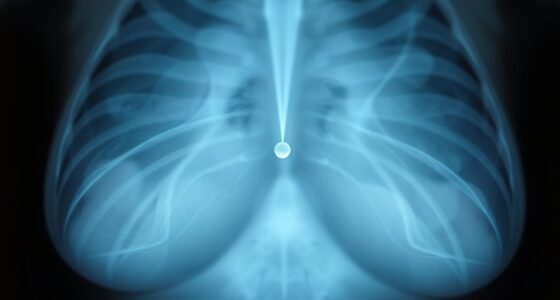

Brustkrebsscreening Mammographie